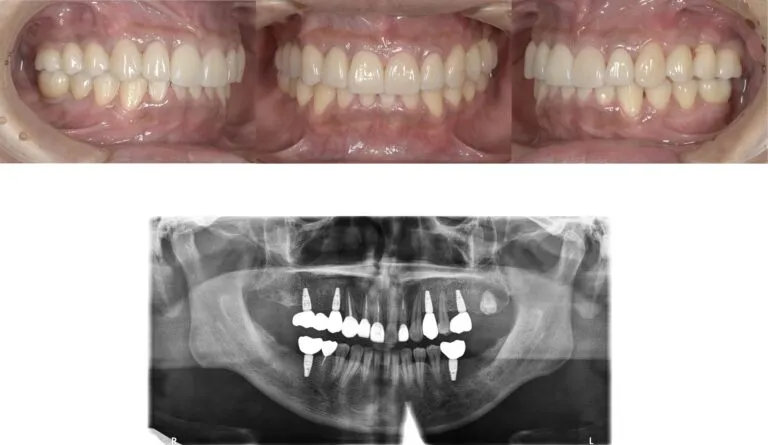

症例3

- 主訴

- 歯が揺れている。全体的な治療を希望

- 治療内容

- インプラント治療、セラミックによる補綴治療

- 治療費

- 450万

- 治療期間

- 1年6ヶ月

- 通院回数

- 50回

- 想定されたリスク

- 将来的な二次カリエス、歯周病の悪化

- コメント

- 入れ歯を使用せずに、しっかり噛めるようになりたいという希望を達成することができました。

before

after